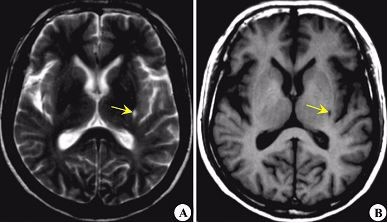

2、第一重要的就是带着自己的父母亲每年做至少一次的体检,因为所有的病几乎都是早发现早治疗,这个病也不例外。所以尽量每年体检给他们做脑部CT以及大血管的彩超检查。